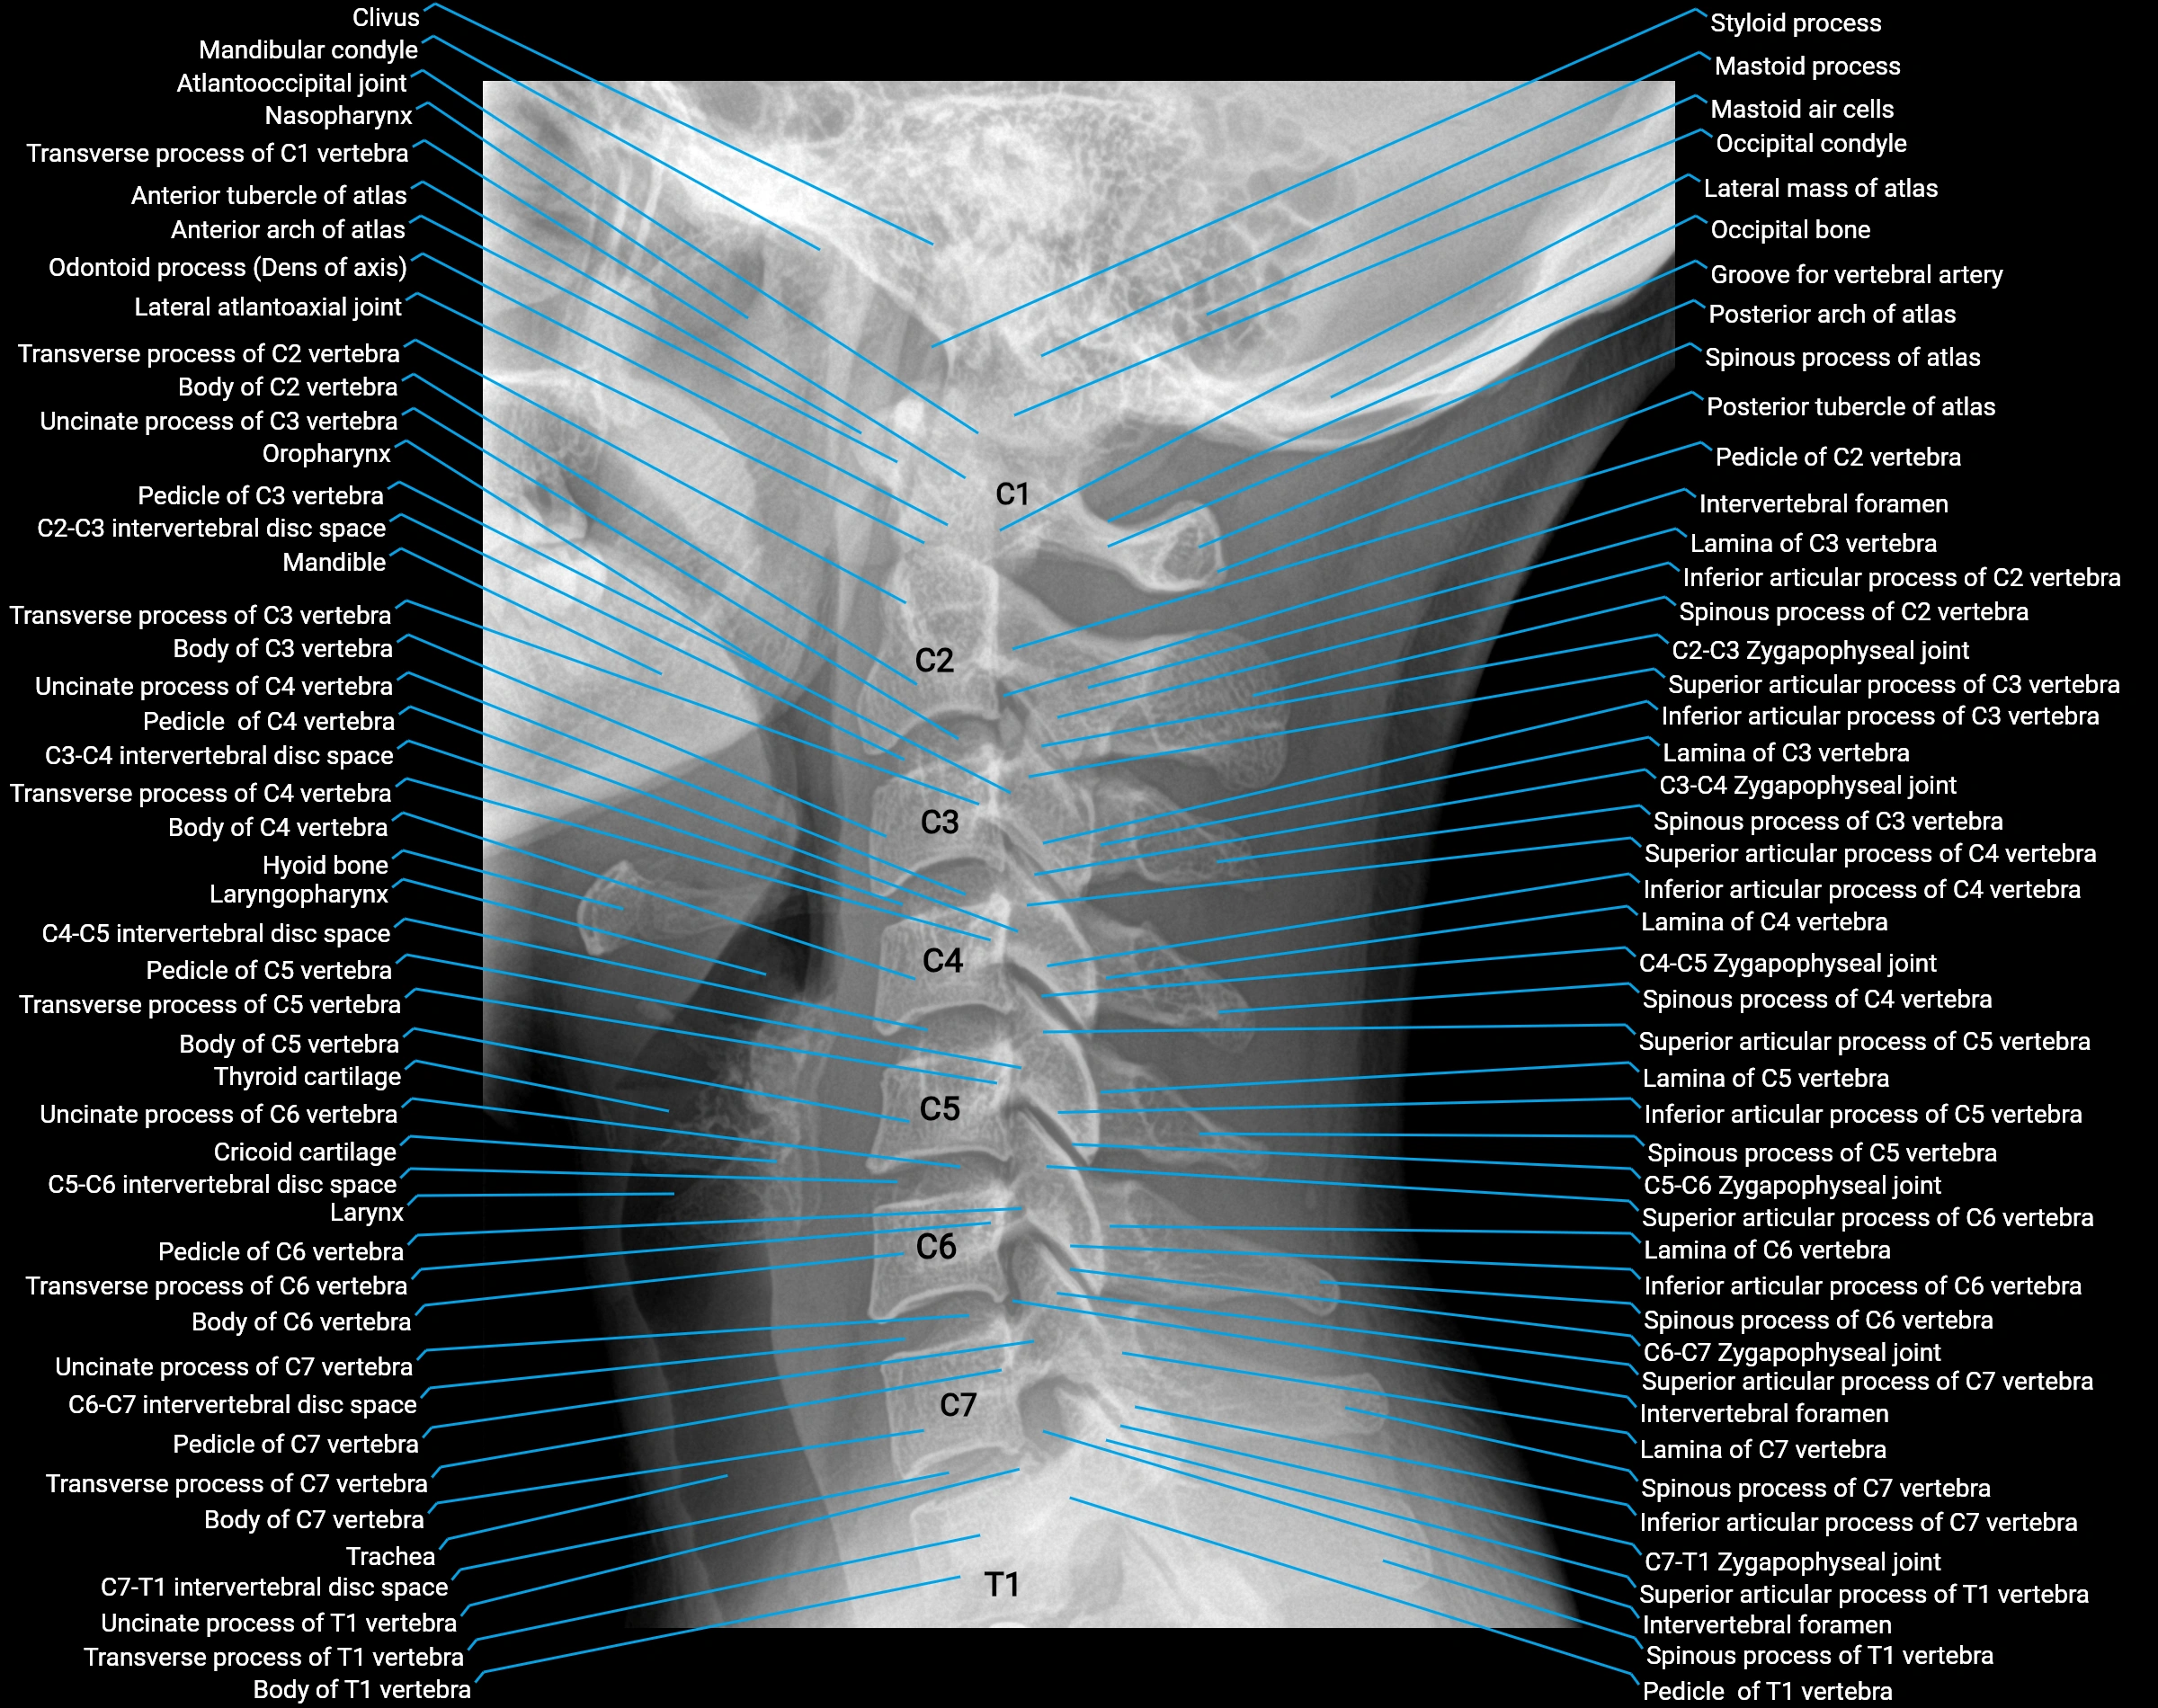

X-ray appearance

Spine radiographs (AP / lateral views):

• Annular epiphysis: Thin, linear bony rim along vertebral endplate margins

• Appearance: Smooth, well-corticated ring

• Age dependence: More conspicuous in children and adolescents

• Fusion: Disappears after complete fusion with vertebral body